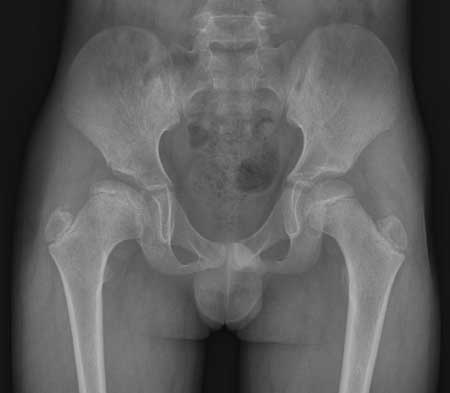

男,12岁,

右侧先天性髋脱位

1右侧髋臼扁平,浅小

2右侧股骨头形状不规则,呈扁平状

3右股骨头向外上方脱位

4右股骨颈短小

右侧髋臼股软骨病继发髋关节半脱位,本病好发于青少年,患者感到腿痛及跛行,运动后加重。

x线表现:1、髋臼浅而宽  2、股骨头骺变扁宽及囊变,干骺端亦有相应增宽   3、由于1所述,所以股骨头可向外上方移位。关节间隙下宽上窄不对称,呈半脱位状态。4、发病早,及时治疗可恢复正常、否则会遗留髋关节半脱位及继发骨性关节炎。本例表现经典,可以诊断。